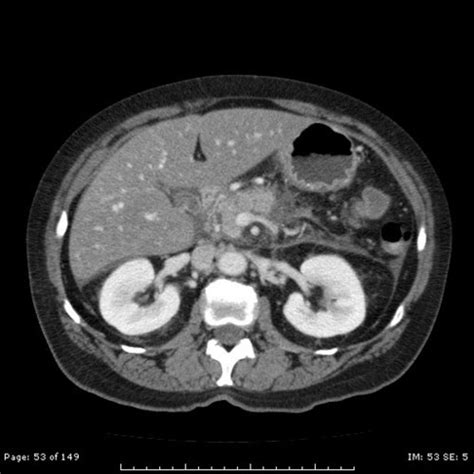

The primary purpose of using a contrast agent during a Computed Tomography (CT) scan is to make specific areas "pop" on the monitor. Without contrast, some organs—like those in the abdomen—might look similar in density, making it difficult to spot subtle abnormalities. When the Ct Contrast agent, which often contains iodine or barium, enters your system, it absorbs X-rays differently than the surrounding tissue. This interaction creates a distinct visual difference in the final image, effectively "highlighting" the targeted area.

• Intravenous (IV) Injection: This is the most common method. The dye is injected into a vein in your arm or hand, allowing it to circulate through your bloodstream to highlight blood vessels, the heart, the liver, or the kidneys.

Tumor Detection To see if a growth has a distinct blood supply compared to healthy tissue.

Vascular Imaging To map arteries and veins to identify blockages or aneurysms.